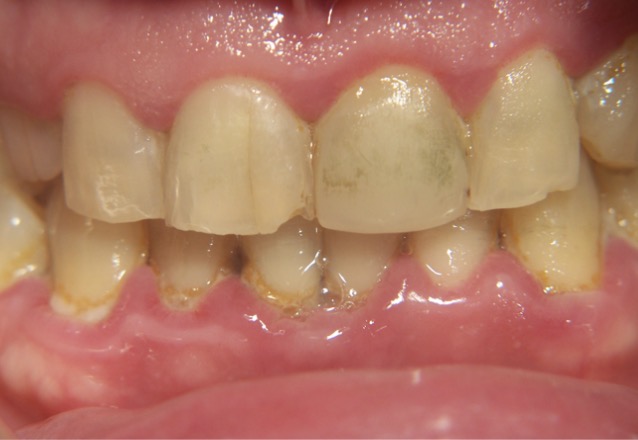

Amelogenesis imperfecta

-Hereditary disorder

-Enamel is very friable and may flake away.

-Scaling procedures should be modified